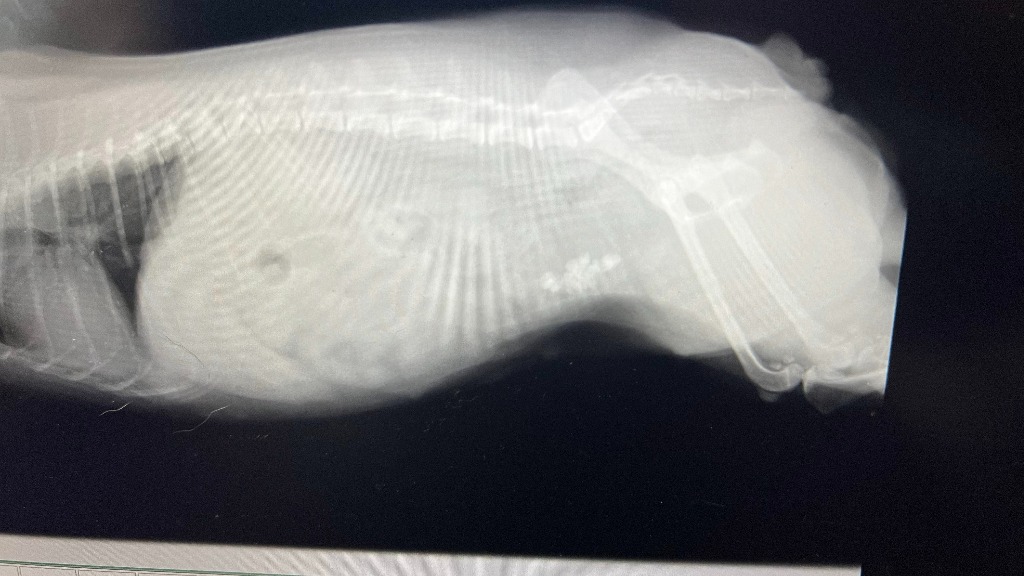

取締役で車監視役のヨークシャーテリアのららの体調が良くないので、病院に行ってきました。

血尿が出て元気がありません。

病院で検査してもらったら、膀胱に胆石が沢山できてました。

それによって膀胱内に傷ができて血尿になっていました。

対処法は、手術しかありません。